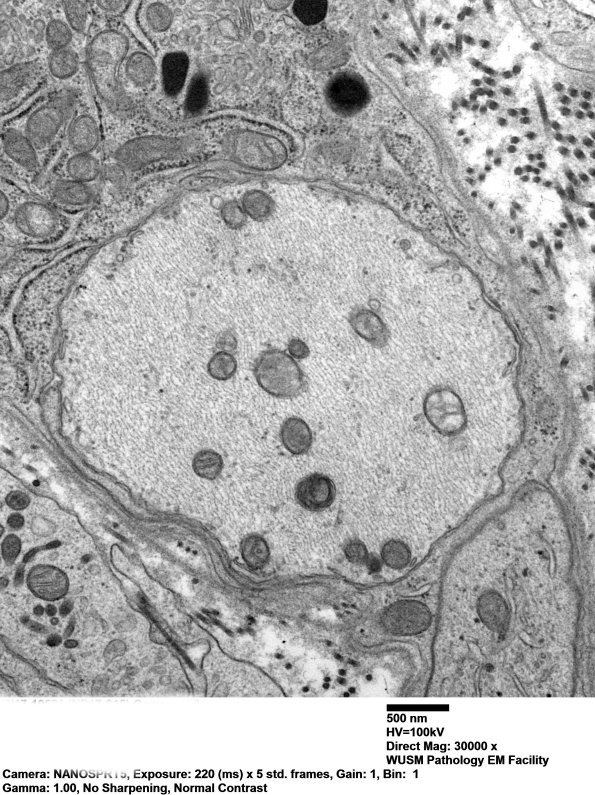

The axonal cytoskeleton is prominent with numerous neurofilaments and microtubules. (electron micrograph)